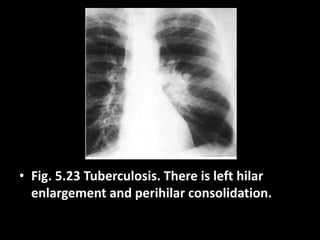

• Fig. 5.23 Tuberculosis. There is left hilar

enlargement and perihilar consolidation.

• Fig. 5.23Tuberculosis. There is left hilar enlargement and perihilar consolidation.